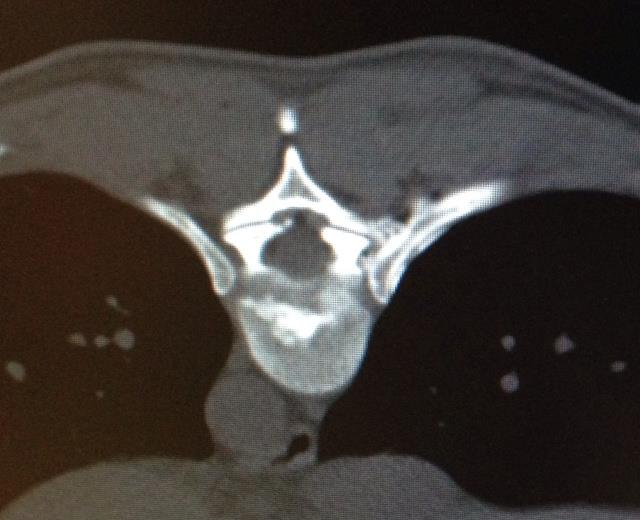

With the help of an X-ray the surgeon inserts a thin needle into the intervertebral disk. Due to the administration of analgetics the entire intervention is nearly pain free. By the help of the needle the surgeon can then insert a glass fiber which carries a laser. The slipped disk can then be vaporized by a laser.

2 thin needles are guided to the joint space

The surgeon will insert a very small needle into the painful joint and will be guided by an X-Ray control. With the help of the needle where a small laser fiber can be inserted the surgeon can now desolate the nerve which causes the pain.